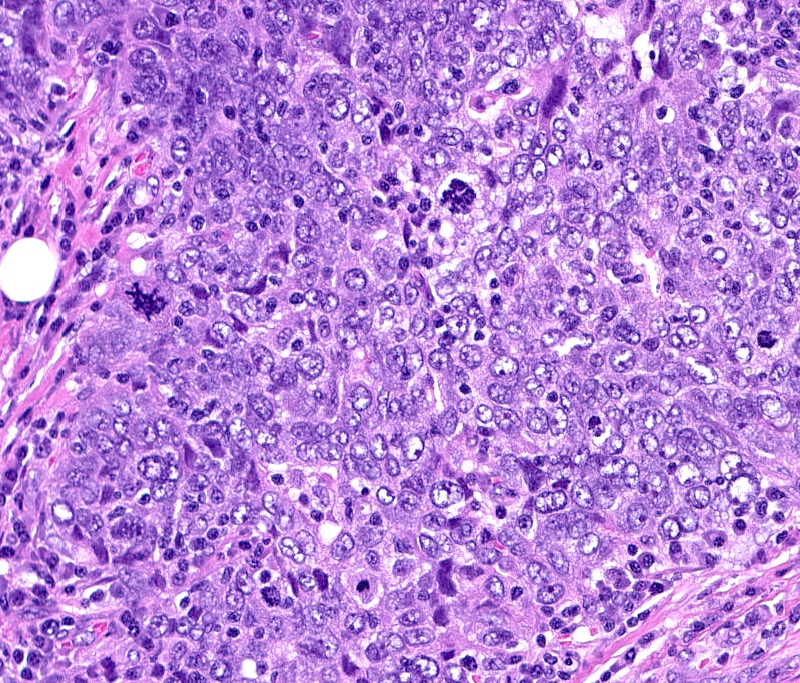

- Basal-like: high grade IDC, NST, solid tumor growth with pushing borders, geographic necrosis, nuclear pleomorphism, brisk inflammatory infiltrate, high mitotic index, high Ki67

- HER2 enriched

- Predominantly IDC, NST of high histological grade

- Tumor cells frequently have pleomorphic nuclei and more abundant eosinophilic cytoplasm than triple negative cancers

- Ki67 proliferative rate is high (20 - 60%)

- Frequently associated with high grade comedo ductal carcinoma in situ

A 67 year old woman underwent a partial mastectomy for a breast tumor shown in the image. Microscopic sections revealed a high grade invasive ductal carcinoma growing as a solid mass with pushing borders, areas of necrosis, brisk mitoses and abundant tumor infiltrating lymphocytes. The tumor was negative for ER, PR and HER2 and was classified as basal-like by gene expression profiling. What other immunostain(s) might be positive?

B. EGFR. Basal-like breast cancers are typically high grade invasive ductal carcinoma of no special type that show solid tumor growth with pushing borders, geographic necrosis, nuclear pleomorphism, a brisk inflammatory infiltrate, a high mitotic index and a high proliferative index with Ki67. Most basal-like breast cancers express basal cytokeratins (keratin 5/6, 14, 17) and EGFR. Answer A is incorrect because while a minor proportion of triple negative breast cancers can express androgen receptor, the prototypical AR positive breast tumor has apocrine features (apocrine carcinoma). Answer C is incorrect because KIT is not characteristically expressed in breast carcinomas. Answer D is incorrect because synaptophysin may be expressed in breast tumors with neuroendocrine differentiation, which typically cluster within the luminal category.